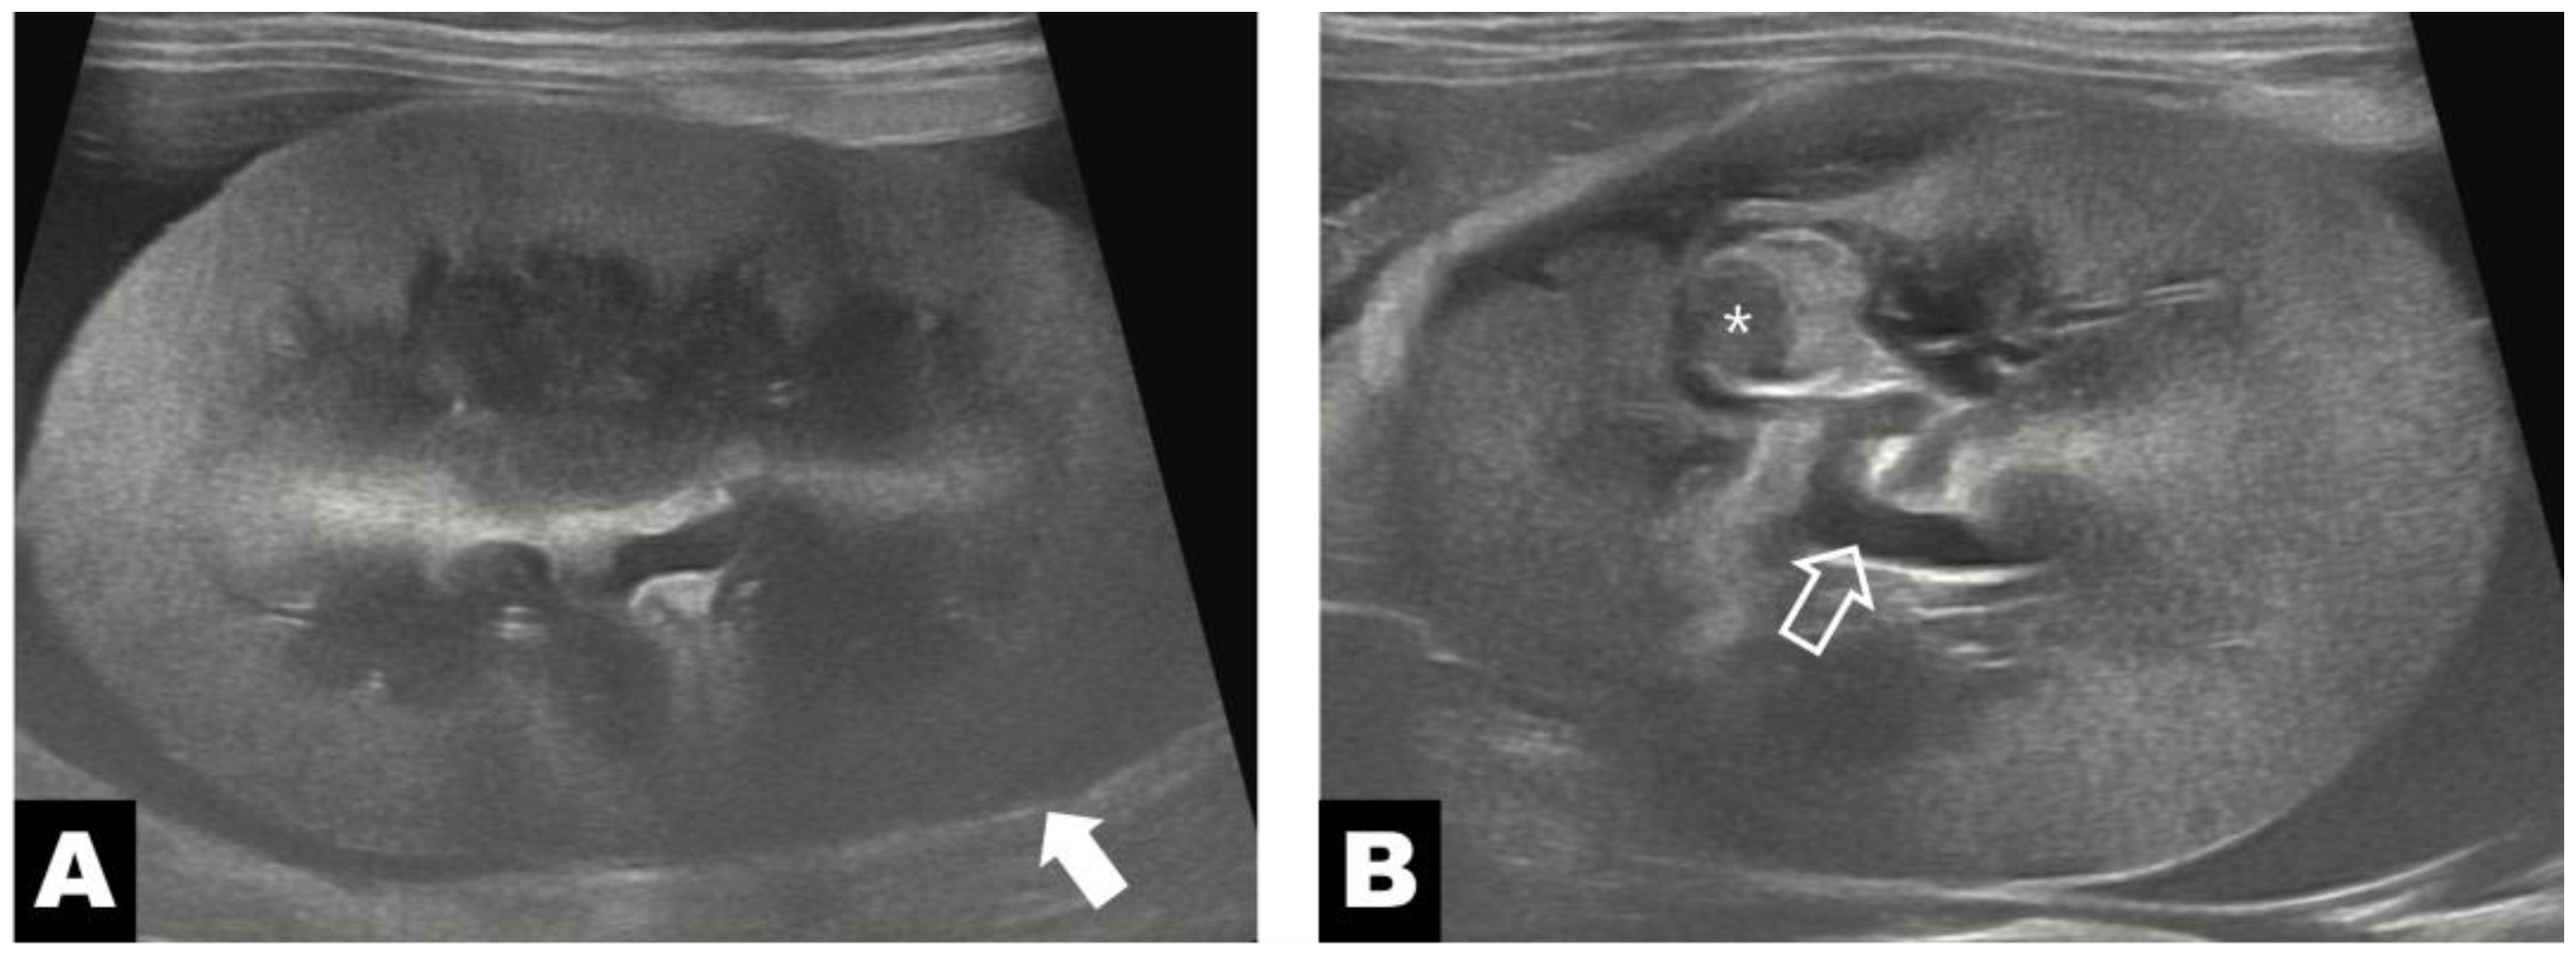

Abdominal ultrasonography performed on postoperative day 4 demonstrated the presence of omental tissue adjacent to the renal parenchyma, along with increased echogenicity of the surrounding perinephric fat and a small amount of residual perinephric fluid (Figure 4A). At this time point, the renal volume was 29.33 cm3. Ultrasonographic measurements obtained at the region adjacent to the diverticular lesion revealed a cortical thickness of 4.7 mm and a medullary thickness of 6.0 mm, resulting in a medulla-to-cortex ratio of 1.28. On follow-up ultrasonography performed on postoperative day 80, the omental tissue remained visible at the same anatomical location (Figure 4B), whereas the previously noted increase in perinephric fat echogenicity and perinephric fluid accumulation had resolved. Follow-up evaluation showed a renal volume of 30.84 cm3, with cortical and medullary thicknesses of 4.5 mm and 6.5 mm, respectively, corresponding to a medulla-to-cortex ratio of 1.44, measured at the same diverticular-adjacent region. Long-term follow-up at 465 days postoperatively was based on owner-reported information obtained by telephone, during which no recurrence of clinical signs was noted.

Figure 4. Postoperative ultrasonographic images of the left kidney. (A) On postoperative day 4, omental tissue (white arrow) is identified at the level of the renal parenchyma, with surrounding increased fat echogenicity. (B) Postoperative day 80, omental tissue (white arrowhead) is observed again at the same location, with no perinephric fluid accumulation observed.